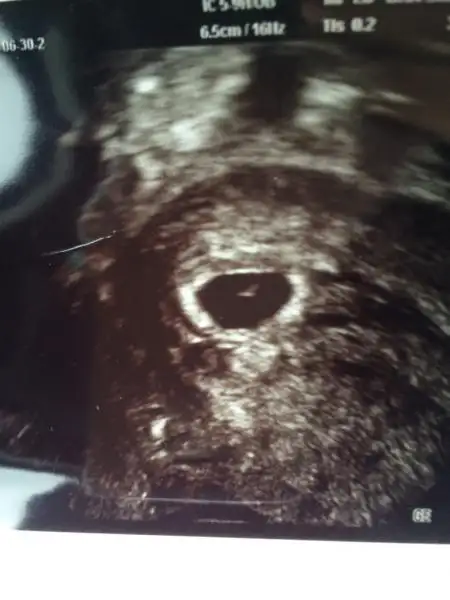

Ilk resmimiz! Simdilik hersey normal. Doktor 5 haftalik dedi. Hormon degerlerim iyi cikmis. Kalp atislari henüz göremedik. Dikkatli ol agir is yapma dedi doktor.haftaya carsamba yine kontrol var. Dua edin kizlar bebegimin kalp atislarini görmem icin. Insallah hersey yolunda gider. Rabbim su mübrek günlerde hayirli haberler almayi nasib etsin.. Amin